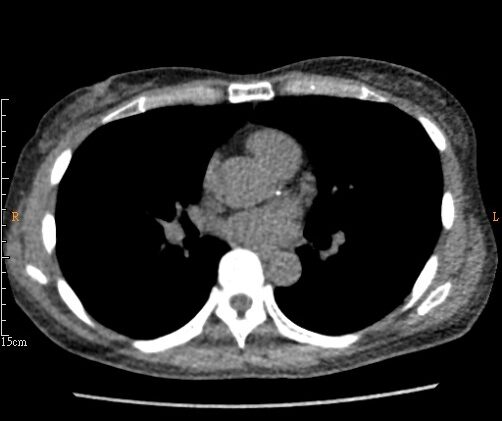

2023年3月,一位62歲留美女科學家返台講學,趁便來做LDCT追蹤檢查。她提到 2019年檢查時曾被我們再次提醒的冠狀動脈鈣化(圖1)有冠心病風險,不以為意,隨後,就爆發心絞痛症狀且裝了支架。此事提醒我們,LDCT的意外發現應引起足夠重視,而非輕忽,建議有諸如此類IFs時,需要提高警覺並請臨床科醫師仔細評估一番,尤其是有三高、吸菸史、肥胖及有冠心病家族史者宜特別注意。

2014年LDCT(重組掃描厚度2.5 mm),即顯示左冠狀動脈前降枝有鈣化,視覺判斷至少有輕度冠狀動脈鈣化(CAC-DRS 1: V1N1)。2019年我們再次對患者提醒對於無症狀者此時應與臨床醫師討論冠心病的風險度與危險因子,尤其有家族病史者。